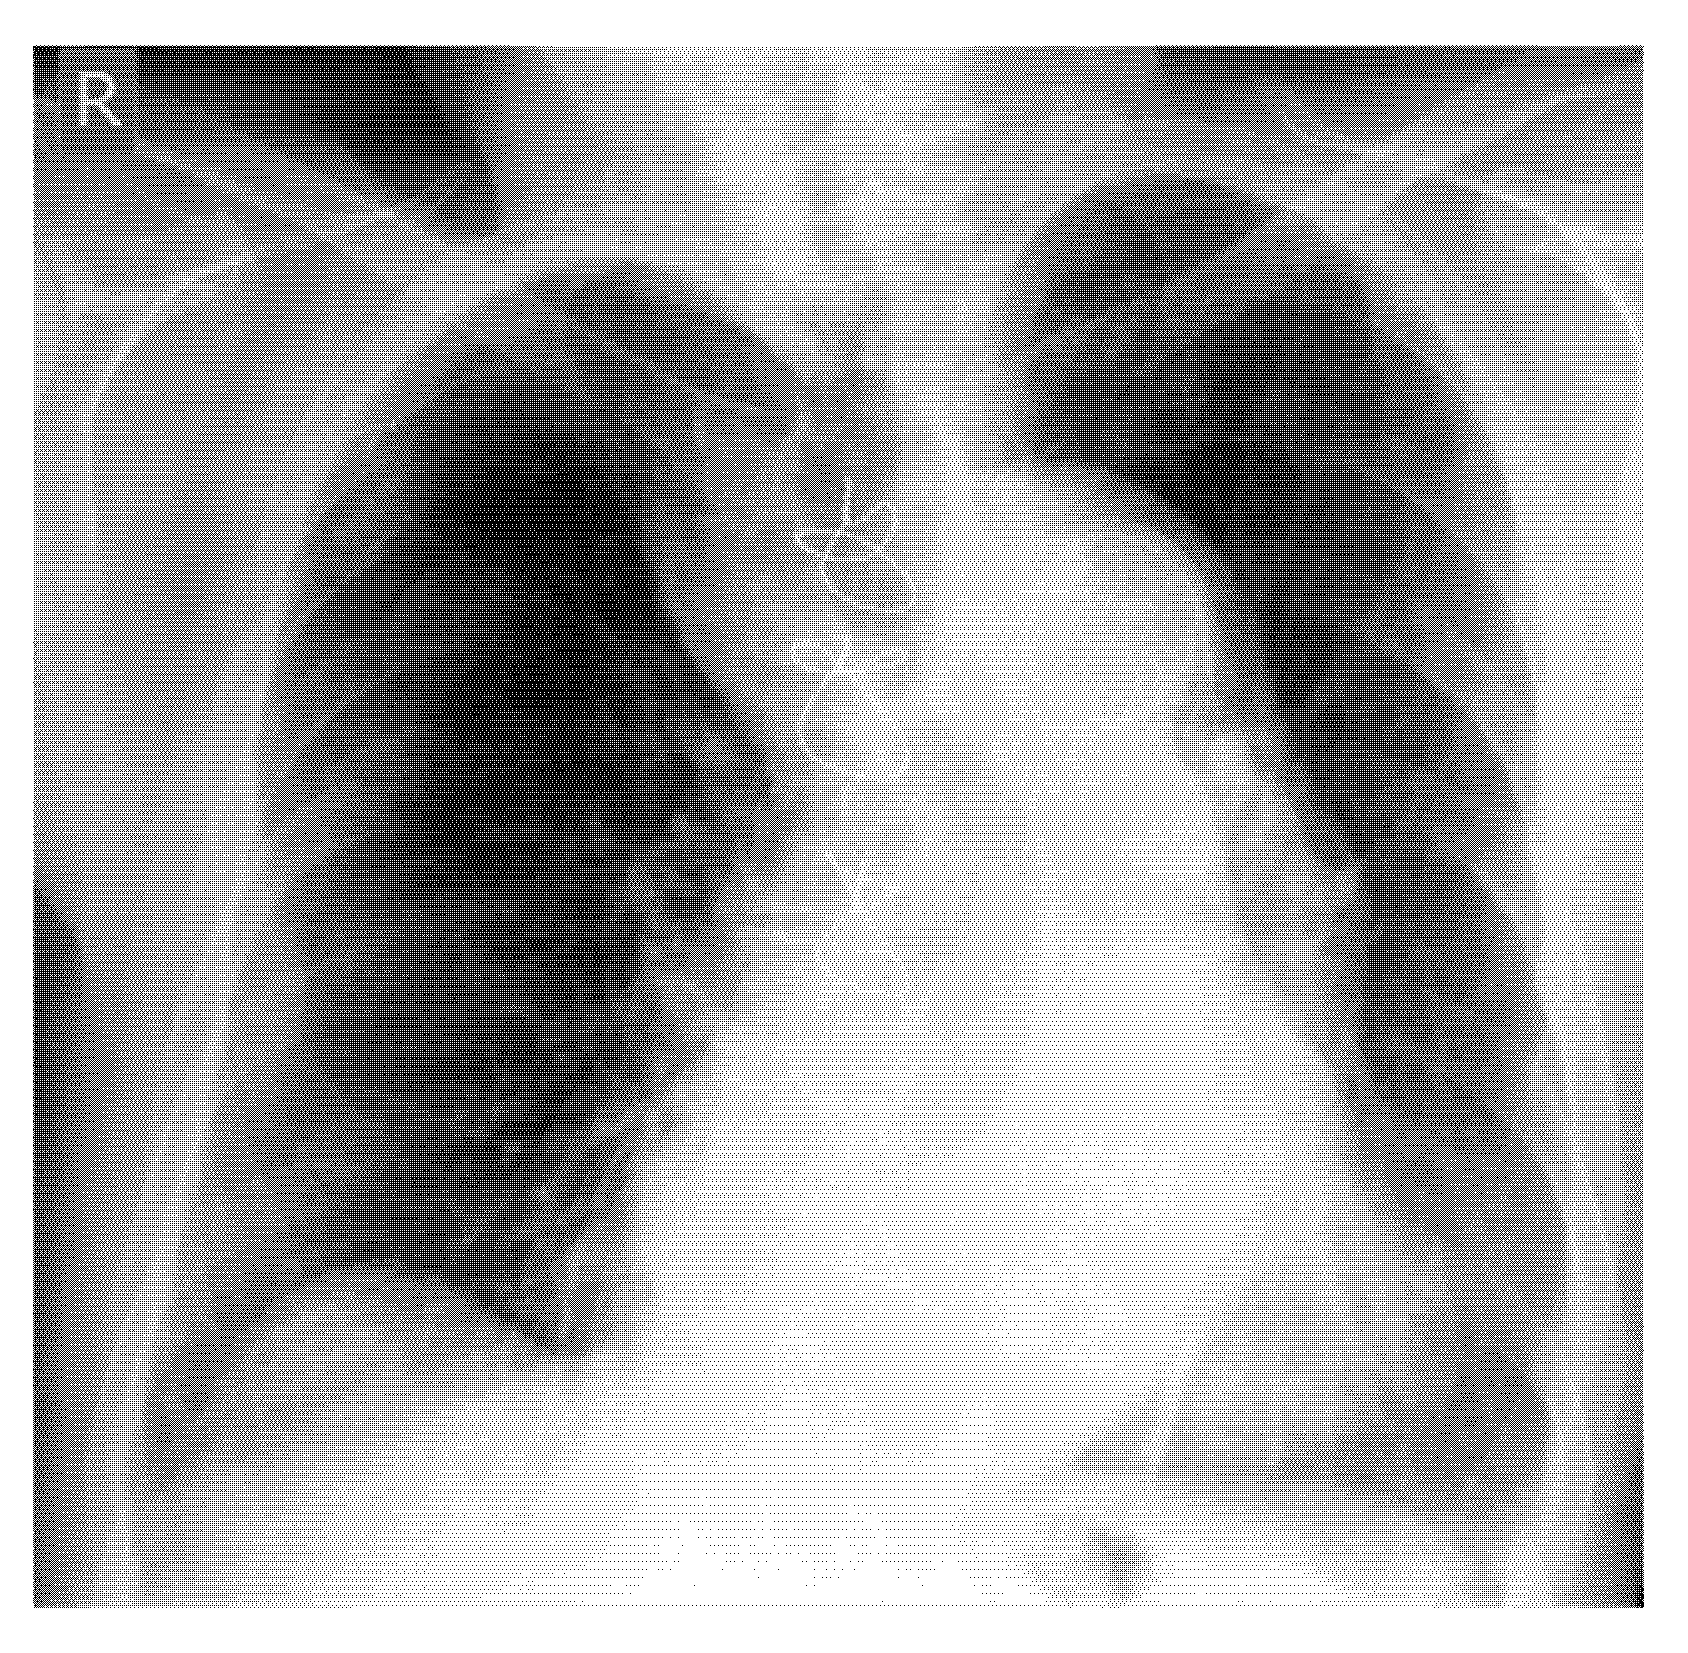

- Example: Common Case of “occult” rib Fractures

- In E-FAST, which is indicated for moderately to severely injured patients with shock, it can be expanded to fracture screening of long tubular bones and open-book fractures if the result of the torso scan is negative for free fluid.